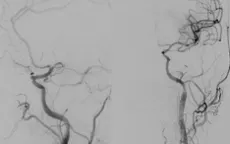

Hai lần tái thông mạch não cứu bệnh nhân đột quỵ

VTV.vn - Bệnh nhân 59 tuổi bị đột quỵ não cấp do tắc mạch lớn đã được cấp cứu kịp thời và hai lần can thiệp tái thông mạch não, phục hồi ngoạn mục sau biến cố nguy hiểm.